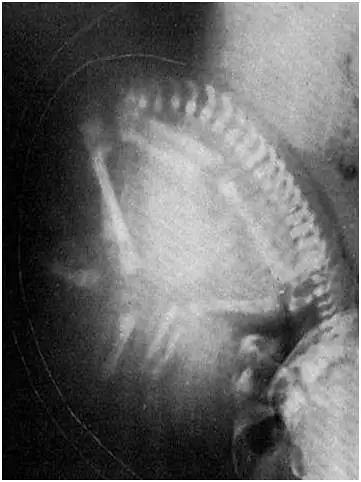

放射科医生的破防瞬间:我竟拍了一位孕妇!

这是一个美好的时代,奔三、奔四的大姐姐们正追赶着三胎的末班车。医院妇产科的床位爆满,四维胎儿彩超却怎么都约不上号。 然而,一提放射科,准妈妈们各个都吓得面容失色,避而远之。 你不知道的是,对放射科医生而言,拍到一个孕妇时,心理阴影的面积是多大…… 申请单一:女,38岁,腰痛查因。 检查结果 胎儿都那么大了! 您腰痛的原因也找到了……

lye6699 2023-05-07 20:0517391 42